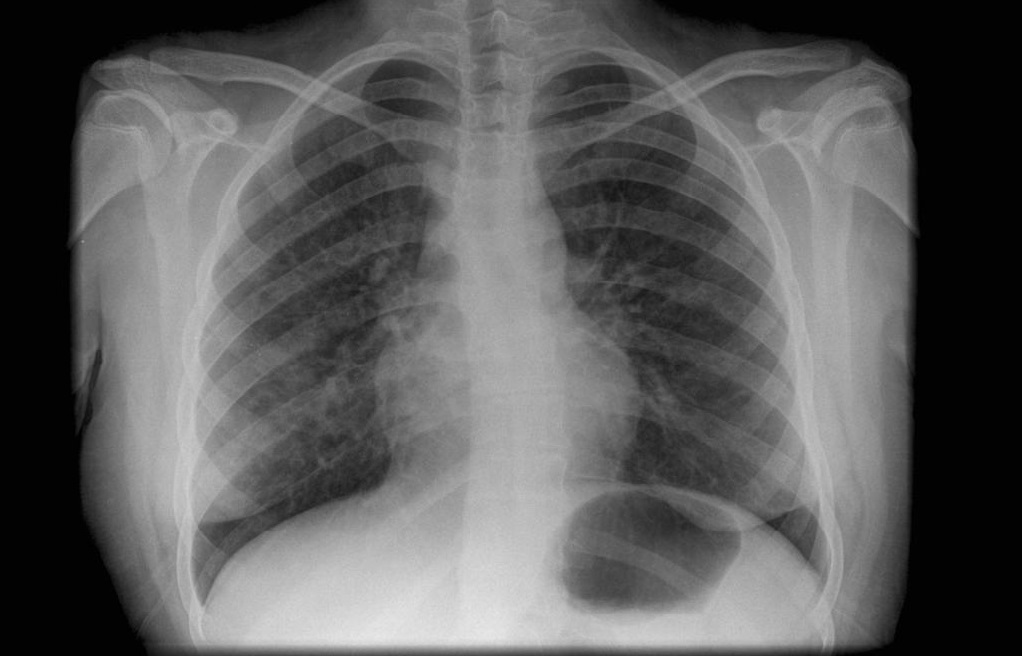

Hypersensitivity pneumonitis (HP) is a relatively new construct, first reported in the early 20th century, despite major aetiological factors (farming, bird husbandry) having been part of human activities for millennia. Initial confirmed HP reports included exposure to farming and forestry (1932) and bird exposure (1965), much more recently than is often assumed. Later changes in occupational and living practices have led to HP associated with isocyanates, machine coolants, indoor mould, hot tubs and other exposures. Evolution of our pathological understanding of interstitial lung disease in general, wider computed tomography utilisation and advances in immunology and genomics have shaped our modern conceptualisation of HP. Examining historical accounts of HP and its causative factors not only considers when the first cases were recognised, but also explores why the disease emerged at specific times and places, and may provide further insights relevant to the mechanisms underlying HP and disease prevention.